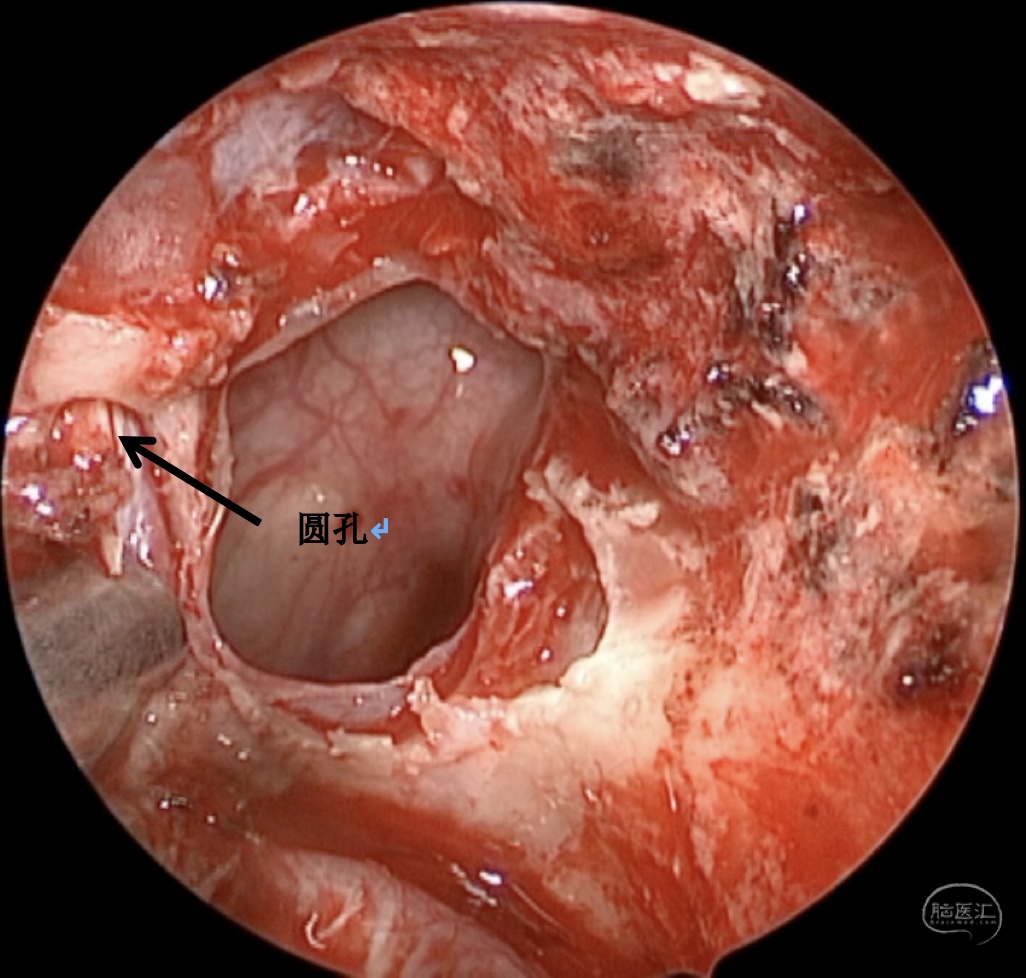

手术方案:内镜经鼻经翼突入路

术中情况:

蝶窦可向翼突根方向过度气化,位于翼管-圆孔连线之外的蝶窦腔隙,称作蝶窦外侧隐窝,是自发性脑脊液漏和脑膜脑膨出的高发区域。蝶窦外侧隐窝脑膜脑膨出伴脑脊液漏在临床上相对少见,这种脑膜脑膨出,如果在出生时出现往往较大,是因为在胚胎形成过程中,神经管未闭所导致。然而,较小的脑膜脑膨出可以多年都不被发现,或者由于外伤、医源性损伤、颅底侵蚀(炎症或者肿瘤)而发生。此外,由于各种原因的颅内压增高,迫使脑组织通过蝶骨的先天性薄弱区疝出,也可以导致该这种疾病发生,本例患者应属于这种情况。